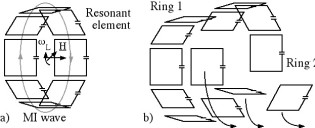

Richard Syms, Evi Kardoulaki and Ian Young

Simon Taylor-Robinson, Chris Wadsworth and Marc Rea (St Mary’s Hospital)

We have developed a magnetic resonance imaging duodenoscope, by combining non-magnetic endoscope components with a thin-film receiver based on a magneto-inductive waveguide. The waveguide elements consist of figure-of-eight shaped inductors formed on either side of a flexible substrate and parallel plate capacitors that use the substrate as a dielectric. Operation has been simulated using equivalent circuit models and by computation of sensitivity patterns. Circuits have been fabricated for operation at 127.7 MHz by double-sided patterning of copper-clad Kapton and assembled onto non-magnetic flexible endoscope insertion tubes. Operation has been verified by bench testing and by 1H MRI at 3T using phantoms. The receiver can form a segmented coaxial image along the length of the endoscope, even when bent, and shows a signal-to-noise-ratio advantage over a surface array coil up to three times the tube diameter at the tip. Initial immersion imaging experiments have been carried out and confirm an encouraging lack of sensitivity to RF heating.

| Mechanical arrangement of metameterial endoscope. |

| Electrical layout of thin film PCB (a), and equivalent circuit models for imaging (b) and electrical testing (c). |

| Arrangement for magnetic resonance imaging with cuboid phantoms (a), body coil image showing effective decoupling (b) and metamaterial coil image, showing segmented field of view (c). |